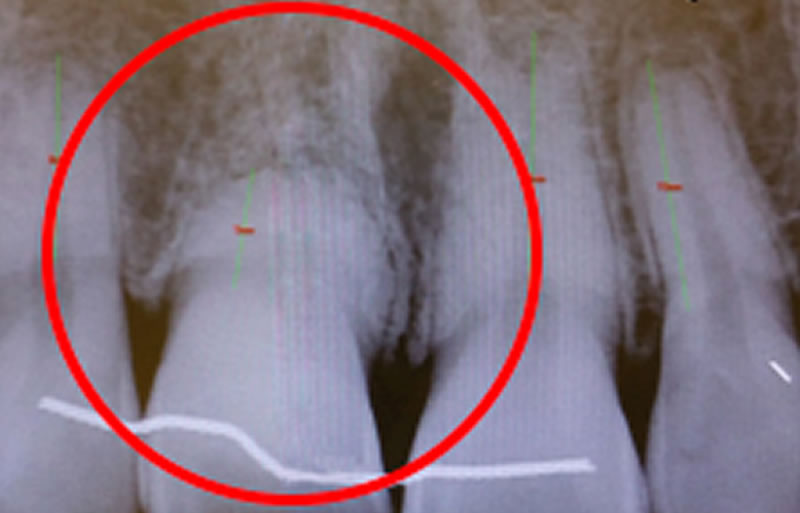

L’implant dentaire peut être posé avant ou pendant la réalisation des greffes osseuses et gingivales, avec l’adjonction de PRP et de PRF. Une option consiste à utiliser une guidance numérique lors de la pose de l’implant. La fabrication d’une couronne céramique cosmétique fixe, qui reconstitue la couronne dentaire naturelle, intervient après l’ostéo-intégration de l’implant dentaire et la maturation des greffes.

L’implant a été positionné dans l’alvéole, aligné avec la racine. À ce stade, un guide chirurgical peut s’avérer extrêmement utile, en particulier pour éviter d’éventuels obstacles anatomiques, tels que des paquets vasculo-nerveux situés dans le trou rétro-incisif.

Après la guérison des tissus mous (gencive) et durs (os alvéolaire), la couronne céramique esthétique a été installée sur l’implant.